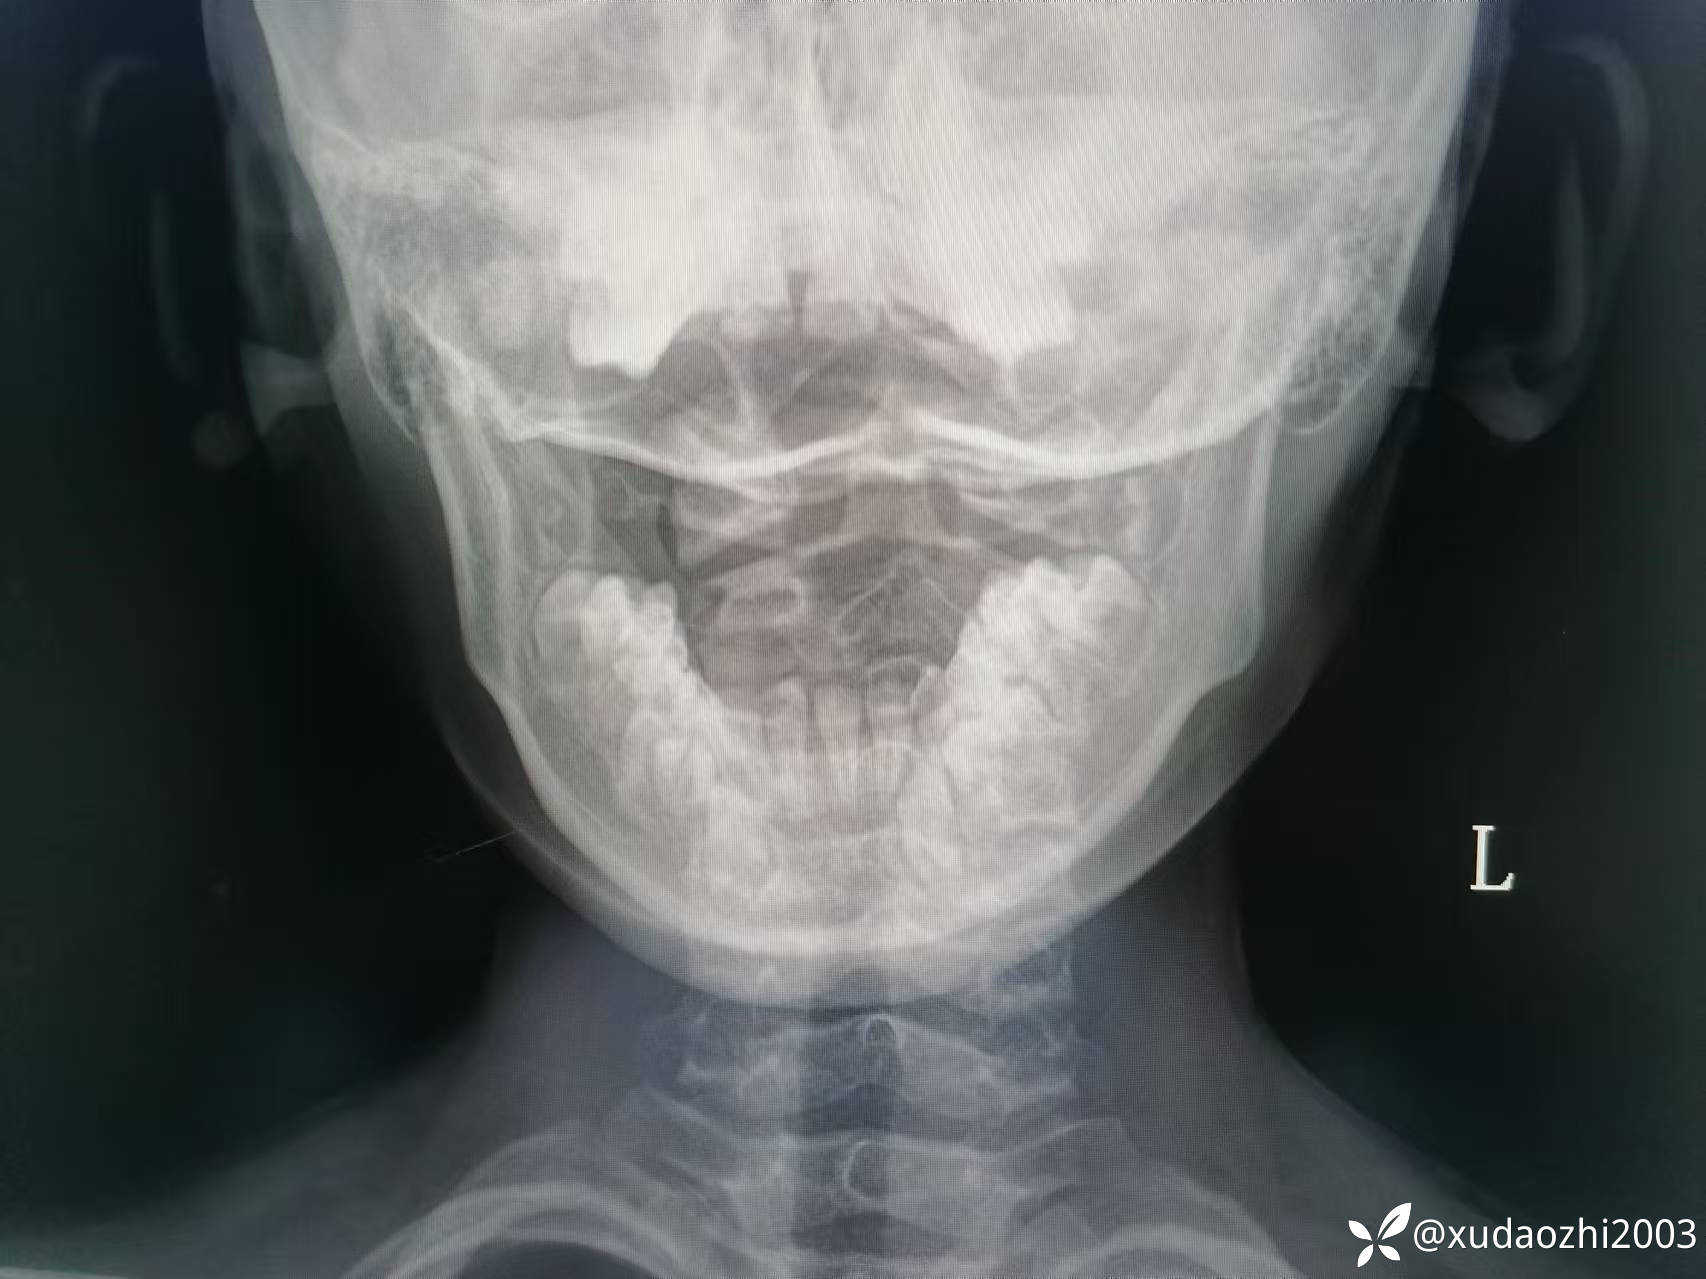

【现病史及既往史】:5月前的某一天曾进食蘑菇,几天后出现恶心呕吐,腹胀,逐渐发展至四肢无力,无法站起,于当地医院给予罗红霉素、补液等对症支持治疗,曾行血液化验检查后除了提示A型肉毒毒素阳性外,余无特殊异常,给予肉毒素针等治疗后好转。但患者嗜睡及晨起不能唤醒呈间断发作,发作时每日早晨约9点才能醒来,醒来时肢体无力,不能活动,约1小时候逐渐肌力恢复,可自主行走。曾去当地省会儿童医院,北京等医院神经科,心理科诊治(监护人诉曾行颅脑及颈髓核磁共振检查未见异常发现,两医院分别行腰穿脑脊液检查结果提示无异常,做过心理筛查未提示心理问题),未见明显改善,曾去北京某中医医院以“颈椎寰枢关节半脱位"为诊断住院治疗,经手法调理颈椎后见明显缓解,后经治疗后出院,但上述症状间断发作,多次请假治疗,但学习成绩未受到影响,学习记忆力无改变。目前每日晨晚醒,呼唤不醒,睡眠期间无抽动、无痉挛、无秽语,醒来后肌力弱、约经1小时后肌力逐渐恢复,醒来后神志清,精神一般,肌力及肌张力稍弱(考虑与废用性有关),生理反射存在,病理反射无。发病前数天患儿与一同学有头部碰撞史,无昏迷,无恶心呕吐。患儿嗜食面食与肉类,不喜水果和蔬菜。